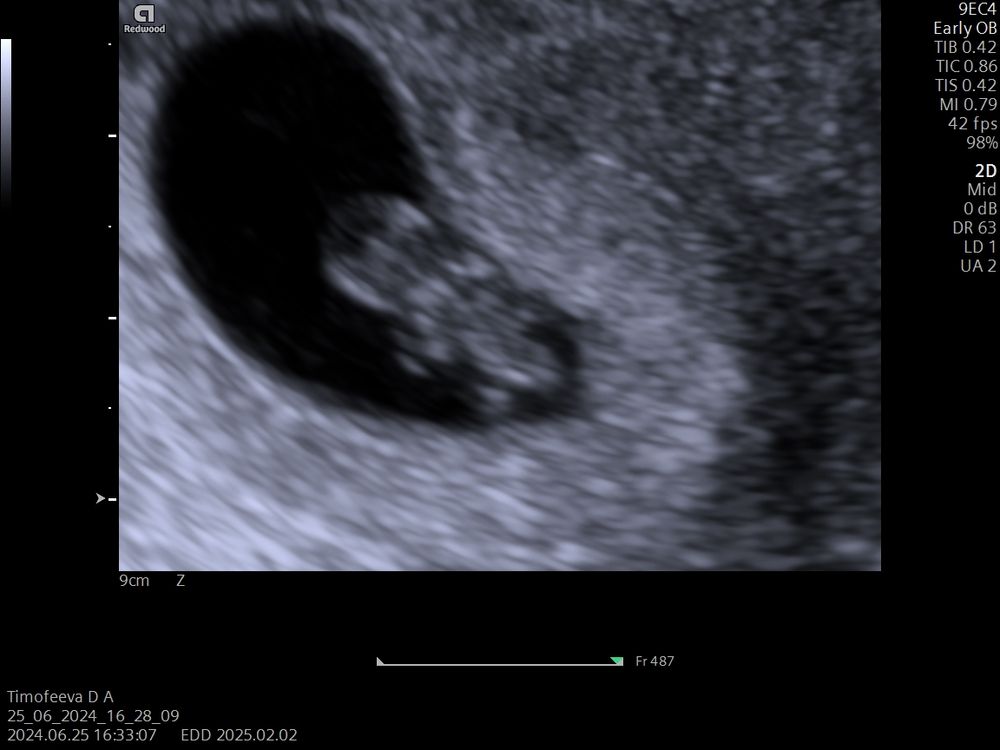

Маленький лапушка ☺️ У меня уже большая бусина🐣 Изображение

25.06.2024